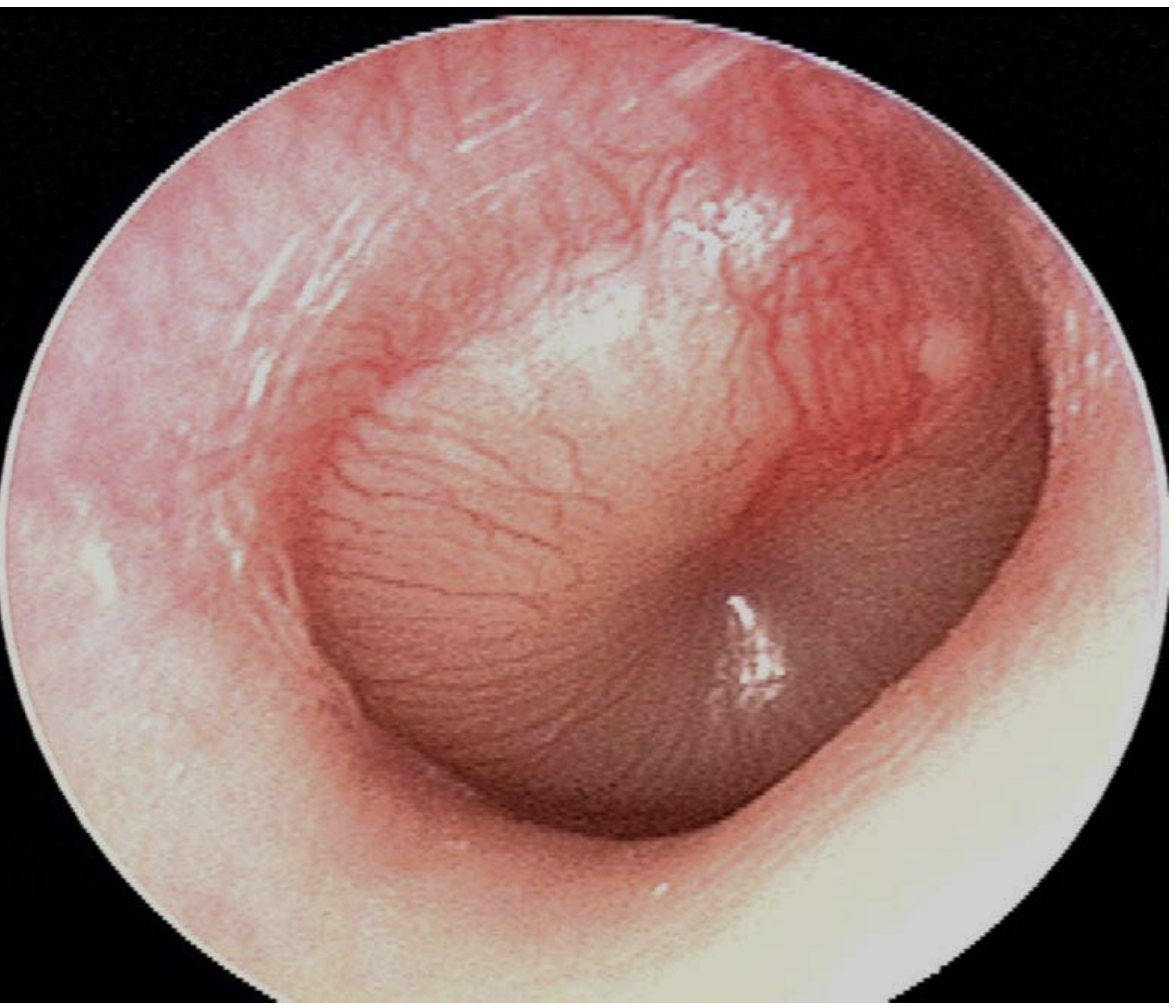

Q

What is the diagnosis and three supportive findings?

A

Acute suppurative otitis media

1. Bulging TM

2. Erythematous TM

3. pus behind TM